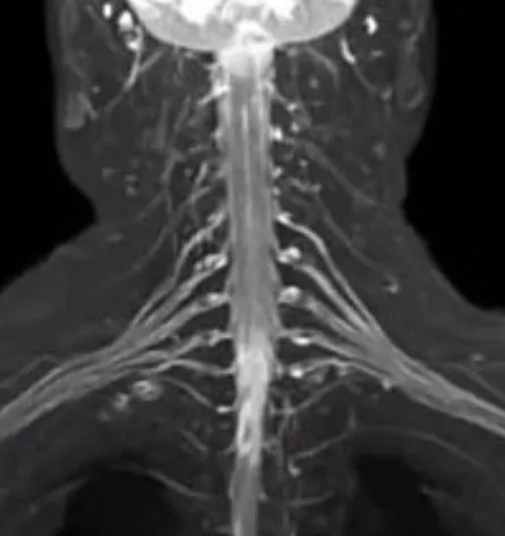

Также есть возможность провести МРТ плечевого сустава с использованием дополнительных последовательностей и МРТ плечевых сплетений.

МРТ плечевого сустава и МРТ плечевых сплетений длится 40 минут.